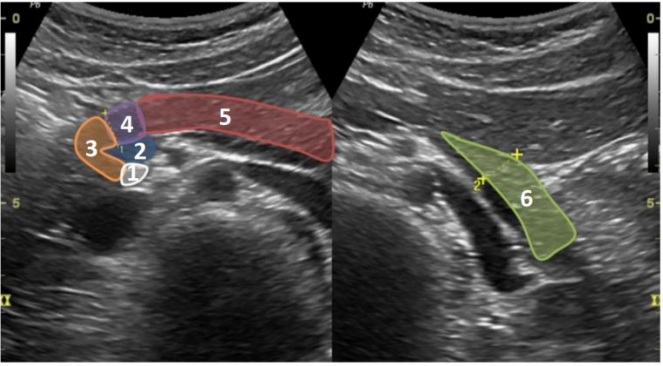

COM BASE NA IMAGEM A SEGUIR, RESPONDA AS QUESTÕES 28 E 29.

Fonte: MANUAL BASICO DE UTRASSONOGRAFIA – ESCOLA PAULISTA DE MEDICINA/2013

Quais órgão (s) está (ão) em evidencia na imagem?